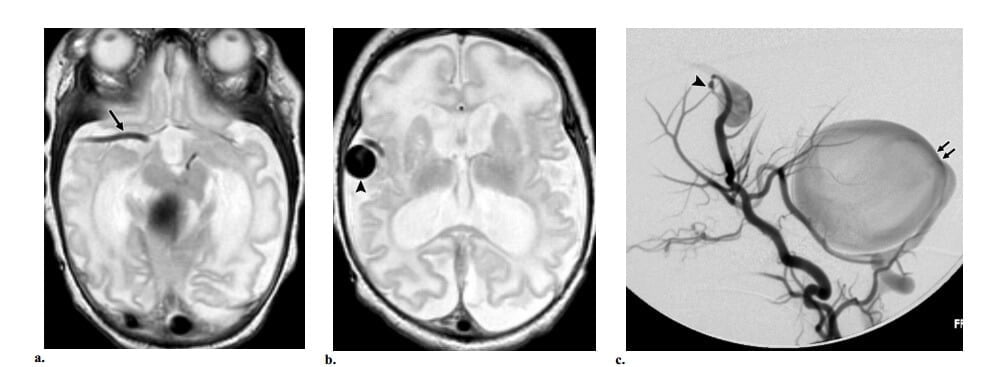

Mặc dù thuộc về nhóm AVM màng mềm “thực sự” , AVF màng mềm không thấy đám rối mạch máu trong nhu mô kinh điển. AVF màng mềm là một phân nhóm đặc biệt của shunt động – tĩnh mạch não và chiếm khoảng 5% các AVM não. Chúng tạo thành shunt động tĩnh mạch thực sự và gồm một thong nối dò trực tiếp giữa động và tĩnh mạch màng mềm mà không có nidus xen vào. AVF màng mềm nằm ở bề mặt não, là tổn thương thường có dòng chảy ca, và trong hầu hết các trường hợp có liên quan với túi tĩnh mạch dãn. AVF màng mềm thường gặp ở trẻ em và thường liên quan với dãn mao mạch xa (telangiectasia) xuất huyết di truyền.

Manh mối để chẩn đoán AVF màng mềm trên hình ảnh cắt lớp gồm sự hiện diện của (a) các mạch máu dãn, chủ yếu ở bề mặt não; và (b) dãn bất đối xứng của động mạch nuôi màng mềm – hoặc là động mạch não giữa, não trước hoặc não sau- thường thấy rõ nhất ở vòng Willis. Các dấu hiệu này có thể dùng để phân biệt AVF màng mềm với AVF màng cứng (hình 9) và có thể đi kèm với túi tĩnh mạch dãn ở bên ngoài nhu mô não.

Hình 9: AVF màng mềm ở trẻ sơ sinh 1 tuần tuổi bị suy tim xung huyết. Bệnh nhân có bệnh sử gia đình dãn mao mạch xa xuất huyết di truyền. (a, b) Axial MRI T2W thấy lớn động mạch não giữa phải ở ngang mức vòng Willis (mũi tên ở a) và một cấu trúc mạch máu dãn lớn ở vùng quanh rãnh sylvien phải (đầu mũi tên ở b), dấu hiệu gợi ý túi tĩnh mạch. Phần trên của cấu trúc flow void lớn khác cũn g nhìn thấy ở hố sau. (c)Chụp động mạch cảnh trong phải thế nghiêng thấy dò dòng chảy cao giữa nhánh động mạch não giữa và túi tĩnh mạch lớn (đầu mũi tên). Dòng ngược chiều của thuốc cản quang đi vào động mạch thân nền khẳng định sự hiện diện của dò dòng chảy cao khác (mũi tên) từ động mạch tiểu não sau dưới. Dò dòng chảy cao và túi tĩnh mạch là các dấu hiệu điển hình ở bệnh nhân bị dãn mao mạch xa xuất huyết di truyền.